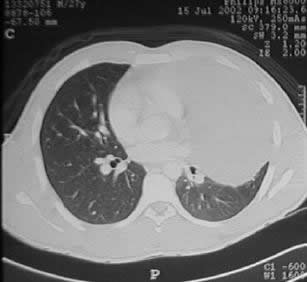

un paciente joven, con un gran tumor del mediastino anterosuperior de rápido

crecimiento, correlacionando su tamaño entre la radiografía

del tórax y los hallazgos tomográficos realizado 15 días

Las experiencias

estadísticas demuestran que el linfoma es la primera posibilidad

diagnóstica a descartar, pudiendo tratarse también de un

timoma o de cualquier otra etiología de los tumores mediastinales